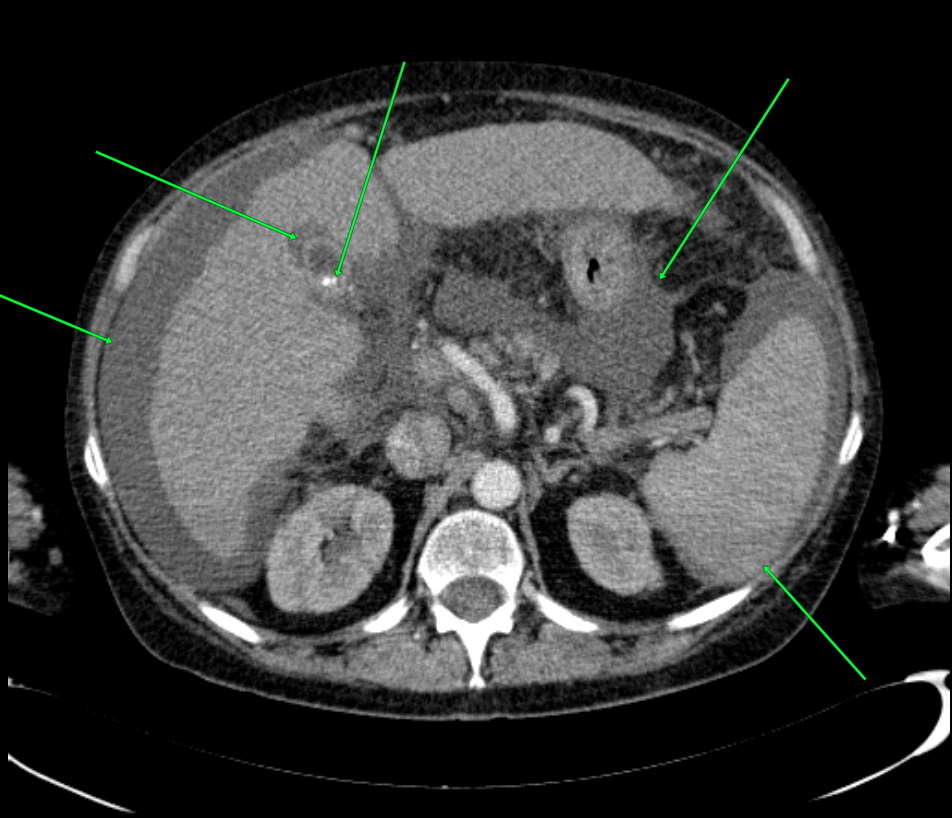

КТ ретроперитонеального фиброза: Изображения и диагностика